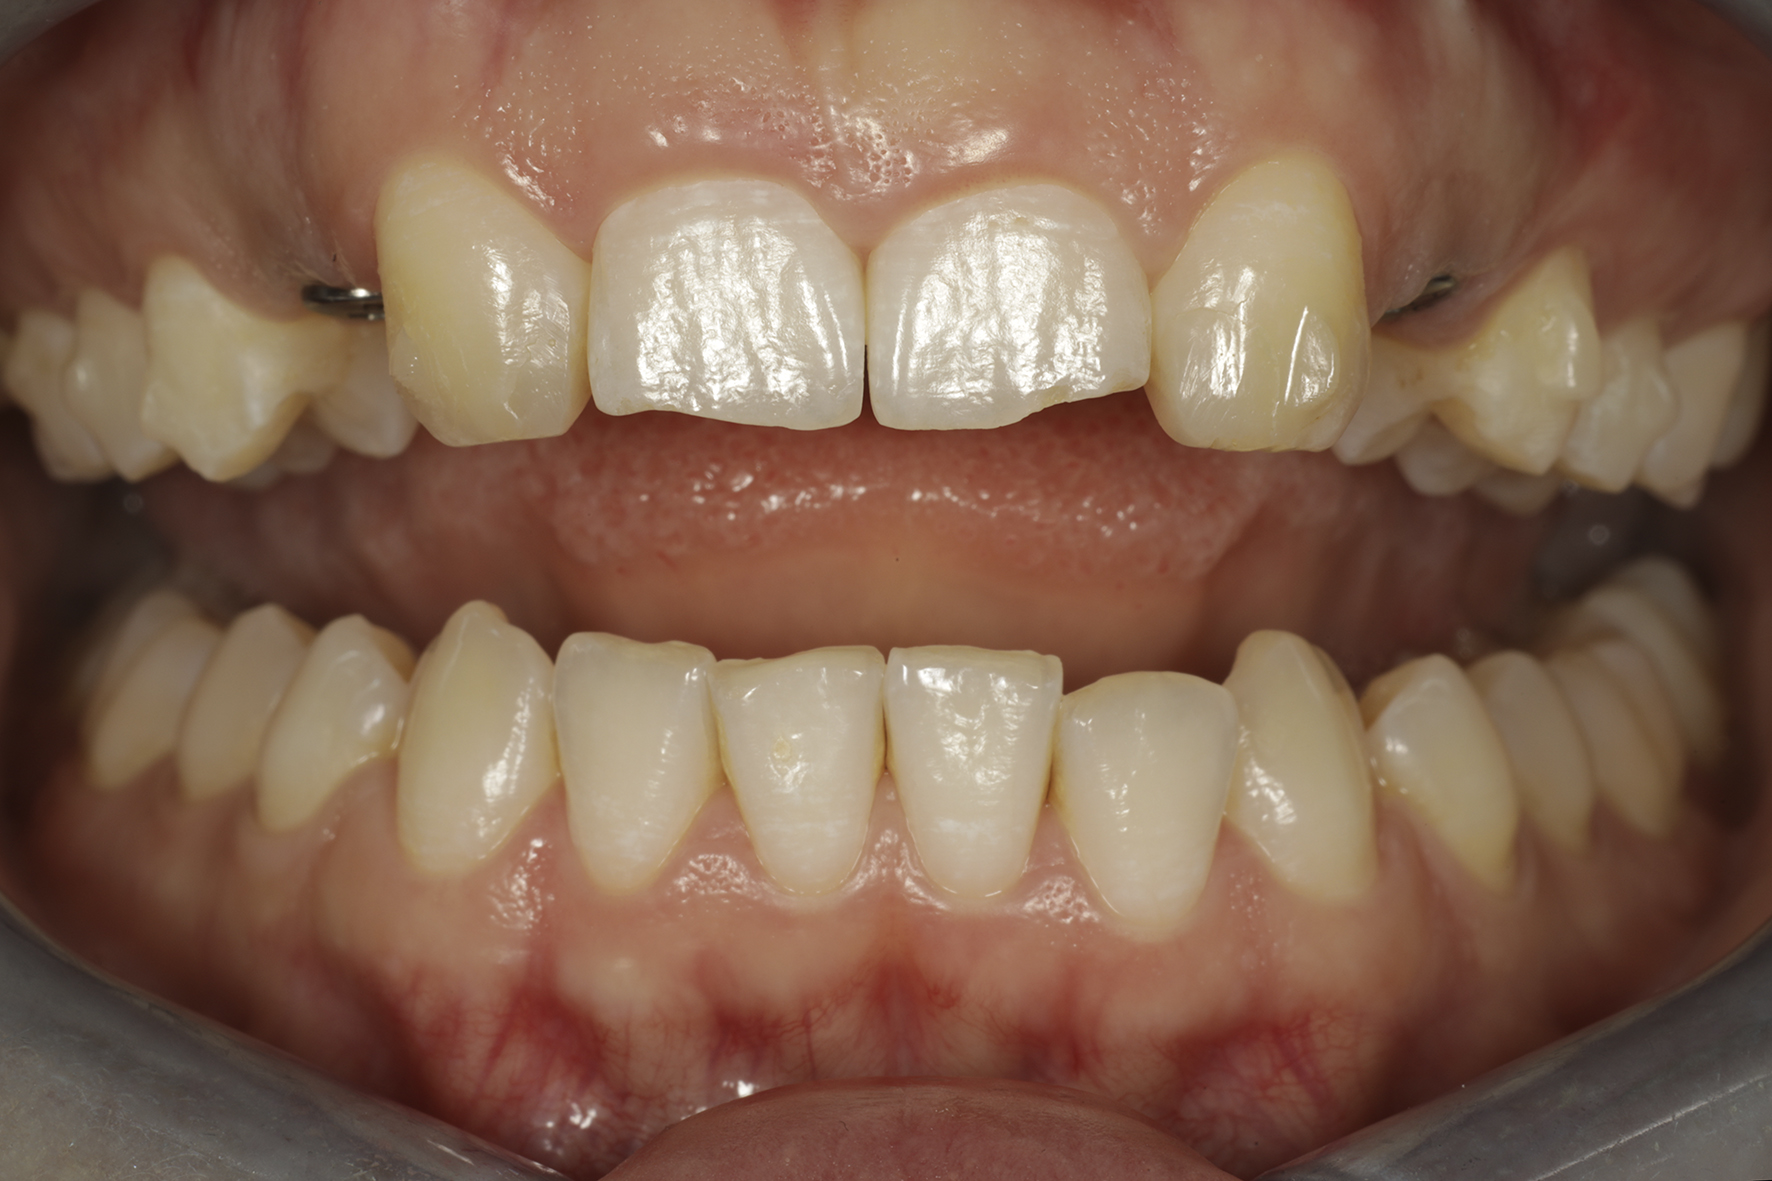

Alkutilanne.

Alkunäkymä huulet retraktoreilla sivuun loitonnettuina.

Näkymä okklusaalipeilin kautta nähtynä.